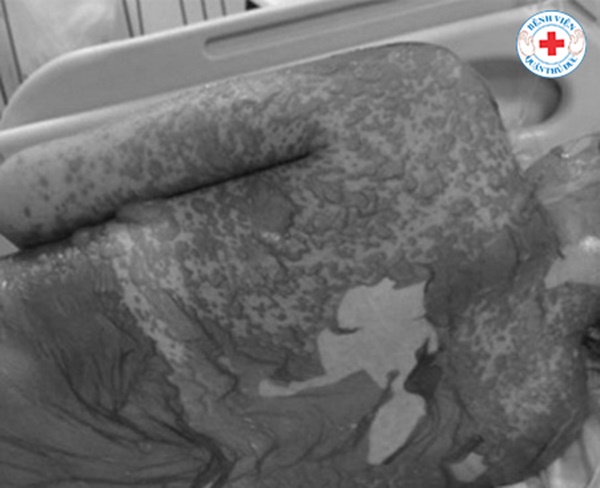

Bệnh nhân có nhiều sang thương đa dạng khác nhau nhưng triệu chứng thường gặp là da bị đỏ lên, nổi bóng nước, lớp thượng bì bị tách ra, tổn thương niêm mạc mắt, miệng, sinh dục. Bệnh nhân sẽ có cảm giác đau như bị phỏng. Một số bệnh nhân sẽ nổi hồng ban. Hội chứng này đa phần liên quan đến phản ứng dị ứng thuốc với một số nhóm thuốc nguy cơ cao như kháng sinh, an thần, giảm đau. Sau vài lần sử dụng, trong vòng 14-21 ngày, bệnh nhân sẽ khởi phát triệu chứng.

Những bệnh nhân bị bóc tróc từng mảng da

Chị Nguyễn Thị Linh Đức, điều dưỡng trưởng khoa Hồi sức tích cực chia sẻ: "Nếu như các trường hợp thông thường khác, bệnh nhân chỉ cần một điều dưỡng để chăm sóc, nhưng với các ca này, tổn thương da lan rộng khắp cơ thể nên việc chăm sóc người bệnh đòi hỏi nhiều thứ hơn. Cần ít nhất khoảng 5 người để tắm rửa và thay băng cho bệnh nhân hằng ngày. Mỗi lần thay băng, chúng tôi đều phải cố gắng làm nhiều cách để giảm tối thiểu sự đau đớn cho người bệnh như chích thuốc giảm đau, động viên người bệnh bằng cách đưa một số hình ảnh mà những bệnh nhân khác cũng bị và đã được điều trị khỏi. Từ đó bệnh nhân mới có động lực mà chiến đấu tiếp".